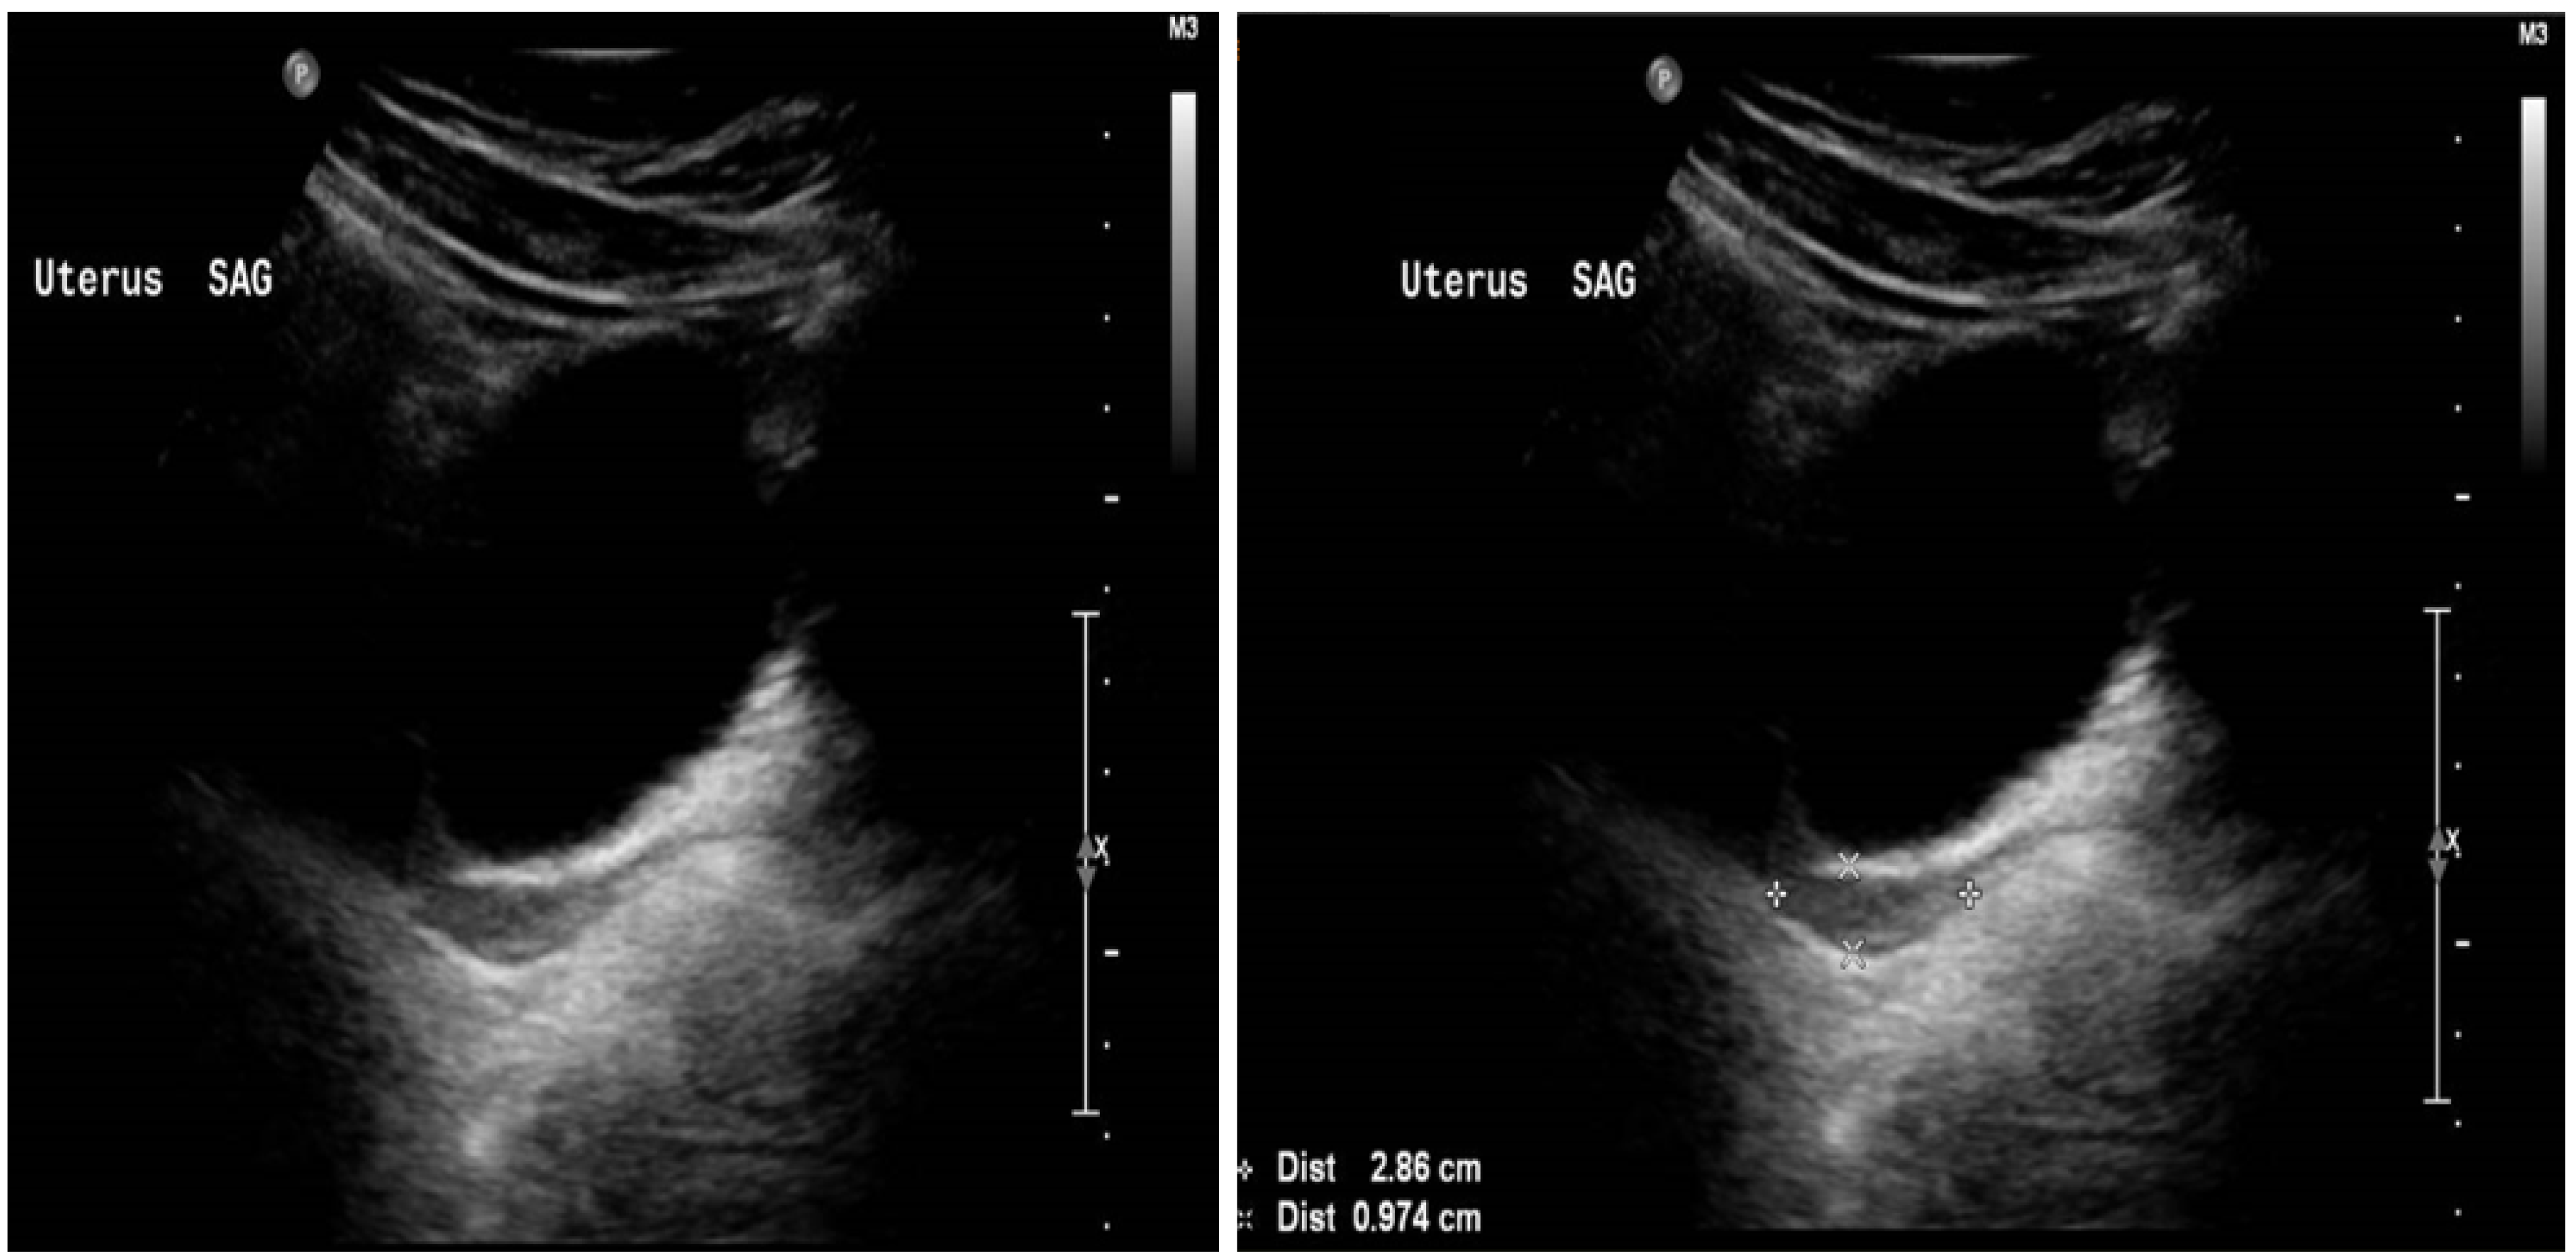

2. Case Report